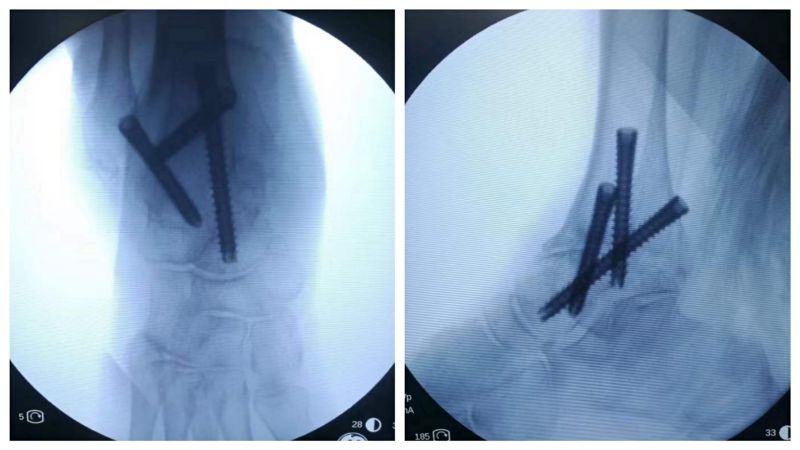

术后X线片显示关节融合位置满意。

通过4个直径0.5cm的小切口完成手术,损伤小,恢复快,更美观。